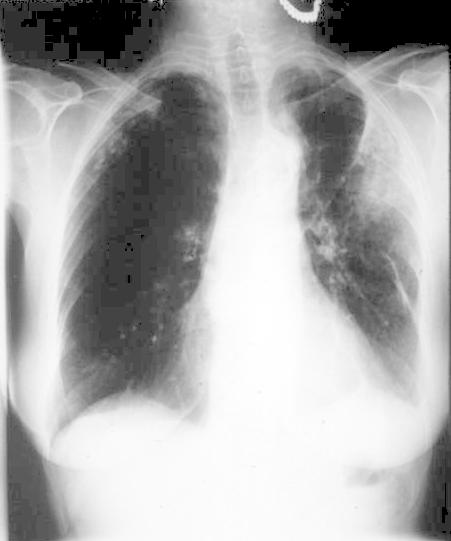

INSPIRATION

Poor Inspiration (picture to the right -->):

* False enlarged heart

* Difficult evaluation of the lungs

Same patient on inspiration (below):

|